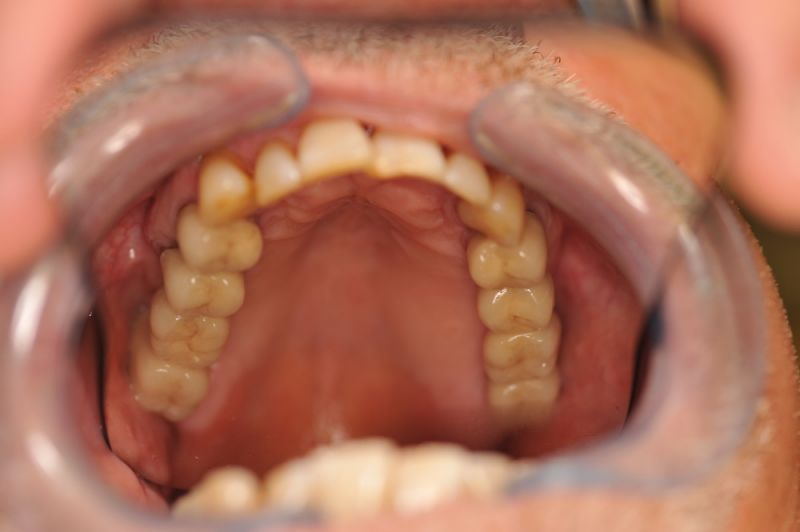

73 jähriger CMD-Patient im Recall

Der Patient hat vor 5 Jahren eine äußerst umfangreiche und komplexe CMD-Behandlung abgesclossen und befindet sich seitdem in einem engmaschigen vierteljährlichen Recall!

Seit 5 Jahren ist der Zustand des Patienten vollkommen unverändert!

Die aktuellen Taschentiefen liegen bei 2 Millimeter! Auch im Bereich der Implantate!

Auch in diesem Fall zeigt sich, dass es gerade bei älteren Patienten sinnvoll ist umfangreiche, festsitzende Versorgungen umzusetzen, so lange sich der Patient noch in einer gesundheitlich guten Konstitution befindet, um dann für die kommenden Lebensjahre Substanz vorzufinden, mit der man "arbeiten" kann.